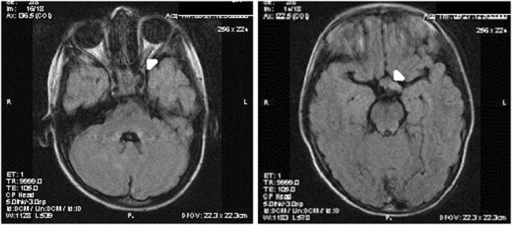

- MRI: 시신경 비대 (kinking/buckling), 시교차 침범

- MRI: 시신경 비대/조영증강

- MRI: 시신경 비대, kinking